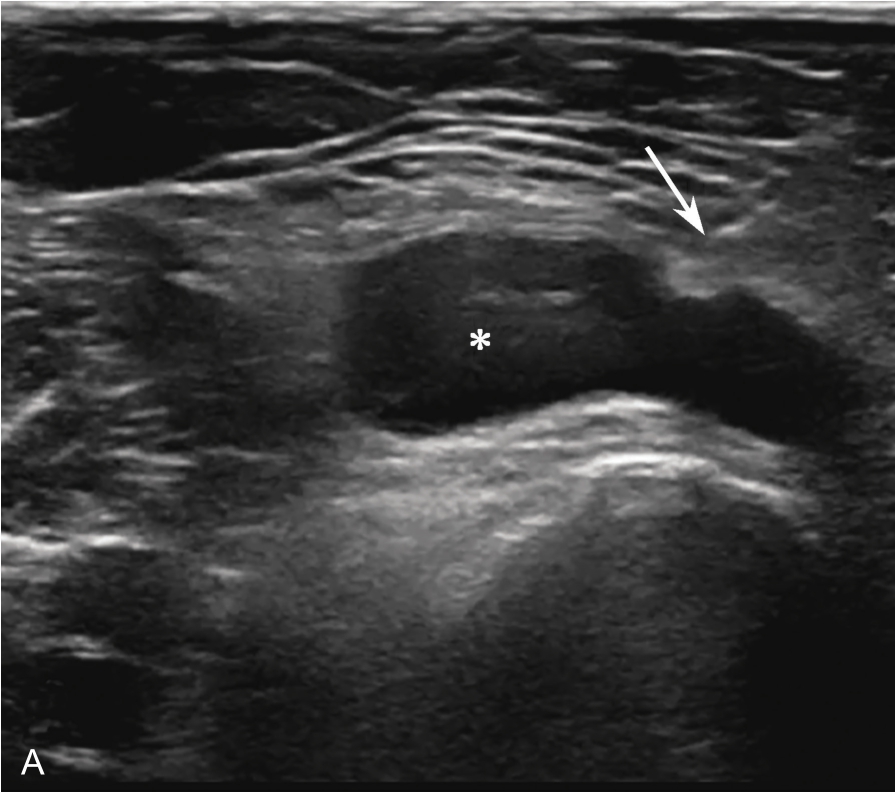

横放在肩关节前方,选择肩峰滑囊较厚或囊液较多处为靶目标(图2-1-2)。

▲ 图2-1-2 肩峰下-三角肌下滑囊炎超声图

星号:肩峰下滑囊增厚伴滑膜增生